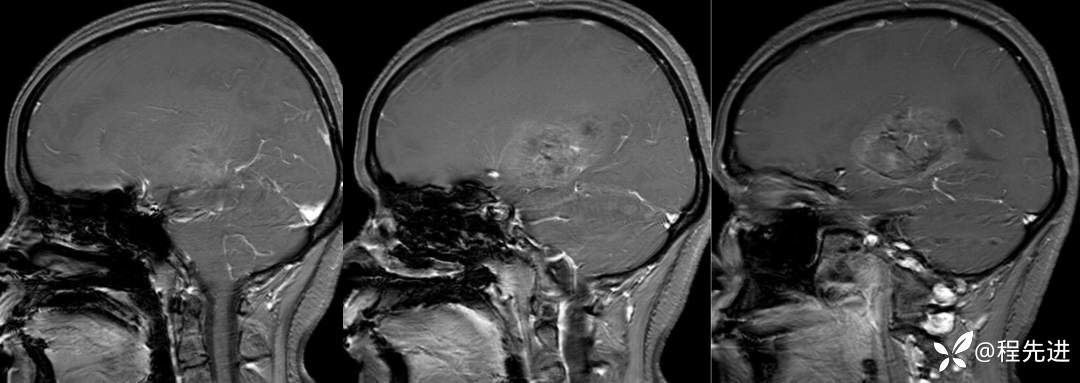

T1+C: